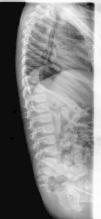

The radiographs of both elbows showed a proximal radioulnar synostosis (Figs. 1 and 2). The radiographs of the spine (Fig. 3) did not reveal any anomalies.